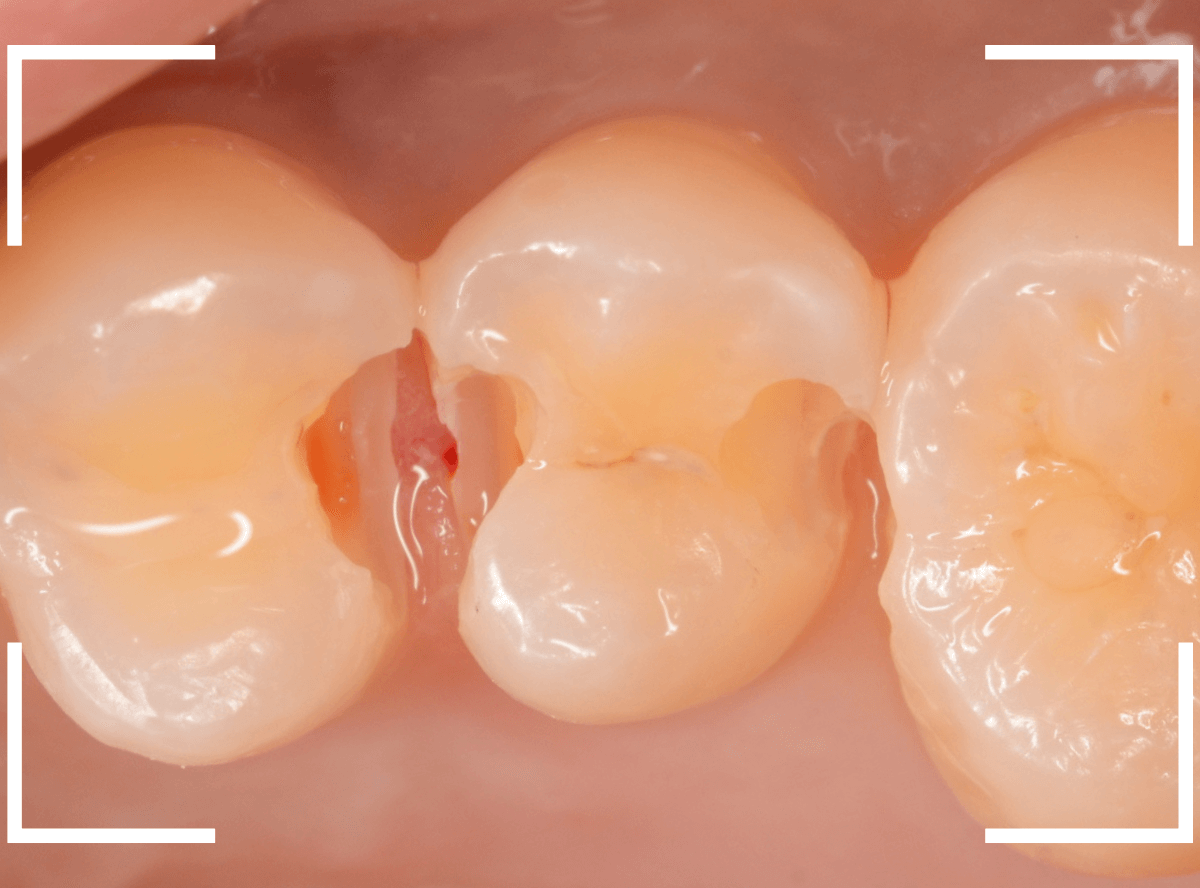

Case.8 大きな虫歯なのに、レントゲンではっきり写らない

こちらも定期検診希望で来院された患者さんです。

お口の中を拝見すると、明らかに虫歯がありました。

3本虫歯になっており、特に中央の小臼歯はかなり大きな虫歯になっているのが予想されます。

治療前にレントゲン写真で虫歯の大きさを確認するつもりが・・・あまりはっきり写ってきません。

患者さんに状況を説明して、歯を少しずつ削りながら虫歯を確認する事になりました。

まず、一番大きな虫歯と思われる部分を小さく削って確認します。

予想通り、虫歯が見えてきました。

隣りの奥歯と一緒に虫歯の治療を進めます。

色が染まっているところがまだ虫歯が残っている部分です。

2本とも、虫歯を全て取り切りました。

特に手前の歯はかなり広めの虫歯になっていました。

最終的に、手前の虫歯の除去も終わったところです。

手前の歯の虫歯は中央の歯まで達していました。

このように明らかに大きな虫歯があると診断されるような状況でも、レントゲン写真でうまく診断できない場合もあります。